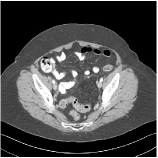

We have conducted experiments on 20 test slices (slice 20, slice 50, slice 100, slice 150 and slice 200 of patient L067, L143, L192, L310) of the Mayo Clinic data. Table I shows the averaged image quality of 20 test images with different methods. From Table I, we observe that Parallel SUPER significantly improves the image quality compared with the standalone methods. It also achieves 1.8 HU better average RMSE compared with Serial SUPER while its SSIM is comparable with Serial SUPER. Fig. 3 shows the reconstructions of L067 (slice 50) and L310 (slice 150) using PWLS-ULTRA, FBPConvNet, serial SUPER (FBPConvNet + PWLS-ULTRA), and parallel SUPER (FBPConvNet + PWLS-ULTRA), along with the references (ground truth). The Parallel SUPER scheme achieved the lowest RMSE and the zoom-in areas show that Parallel SUPER can reconstruct image details better.